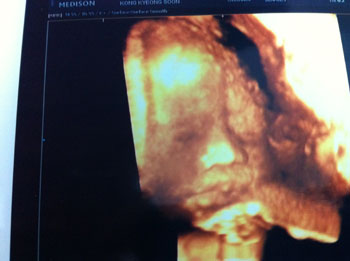

そして、やっと撮れたショットがこちら!

あらまぁ、私のおじいちゃんそっくり!この鼻といい、への字の口といい、じいちゃんだ(笑)女の子なのに、じいちゃん似……。この偉そうな表情たるや、圧巻である……

あまりにもおじいちゃんに似ていたので、父親に写真を送った。じいちゃんと一緒にクルクリの写真を見たらしく、じいちゃんがすごく喜んでいるとのこと。じいちゃん孝行をひとつできた気分になった。